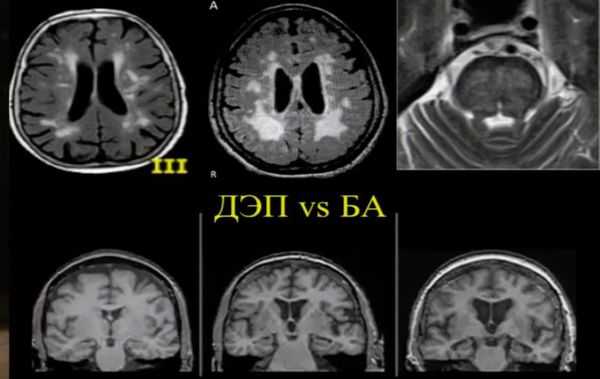

МРТ и КТ проводят для выявления поддающихся лечению причин деменции и нарушений, которые могут усугубить симптомы. Структурные изменения по данным магнитно-резонансной томографии являются более прогностически значимыми для дальнейших изменений в когнитивной сфере, чем биомаркеры цереброспинальной жидкости. По данным магнитно-резонансной томографии, признаки цереброваскулярного заболевания, такие как лейкоареоз и множественные подкорковые лакунарные инфаркты, чаще наблюдаются у пациентов с болезнью Альцгеймера, чем в контрольной группе. [7] Асимметричная атрофия медиальных отделов височной доли также не исключает сосудистую деменцию.

Описана смешанная модель патогенеза болезни Альцгеймера, которая предполагает взаимодействие церебральной амилоидной ангиопатии с сосудистыми факторами на ранних стадиях патологического процесса. Предполагается, что синергия между накоплением амилоида и цереброваскулярной патологией может инициировать дальнейшую дисфункцию нейронов и нейродегенерацию. [8] В этом отношении церебральные микрокровоизлияния, выявляемые в режиме Т2 градиентного эхо на магнитно-резонансной томографии, являются дополнительным и доступным диагностическим маркером, повышающим диагностическую значимость лейкоареоза и свидетельствующим в пользу церебральной амилоидной ангиопатии или гипертонической микроангиопатиии, особенно в случаях смешанной патологии и тяжелого когнитивного дефицита.

Локализация церебральных микрокровоизлияний является дифференциально-диагностическим признаком ведущего патологического процесса. В случае болезни Альцгеймера наблюдается корковая локализация микрокровоизлияний, в случае дисциркуляторной энцефалопатии или сосудистой деменции будут визуализироваться микрокровоизлияния в глубинных отделах мозга. [9] [10]